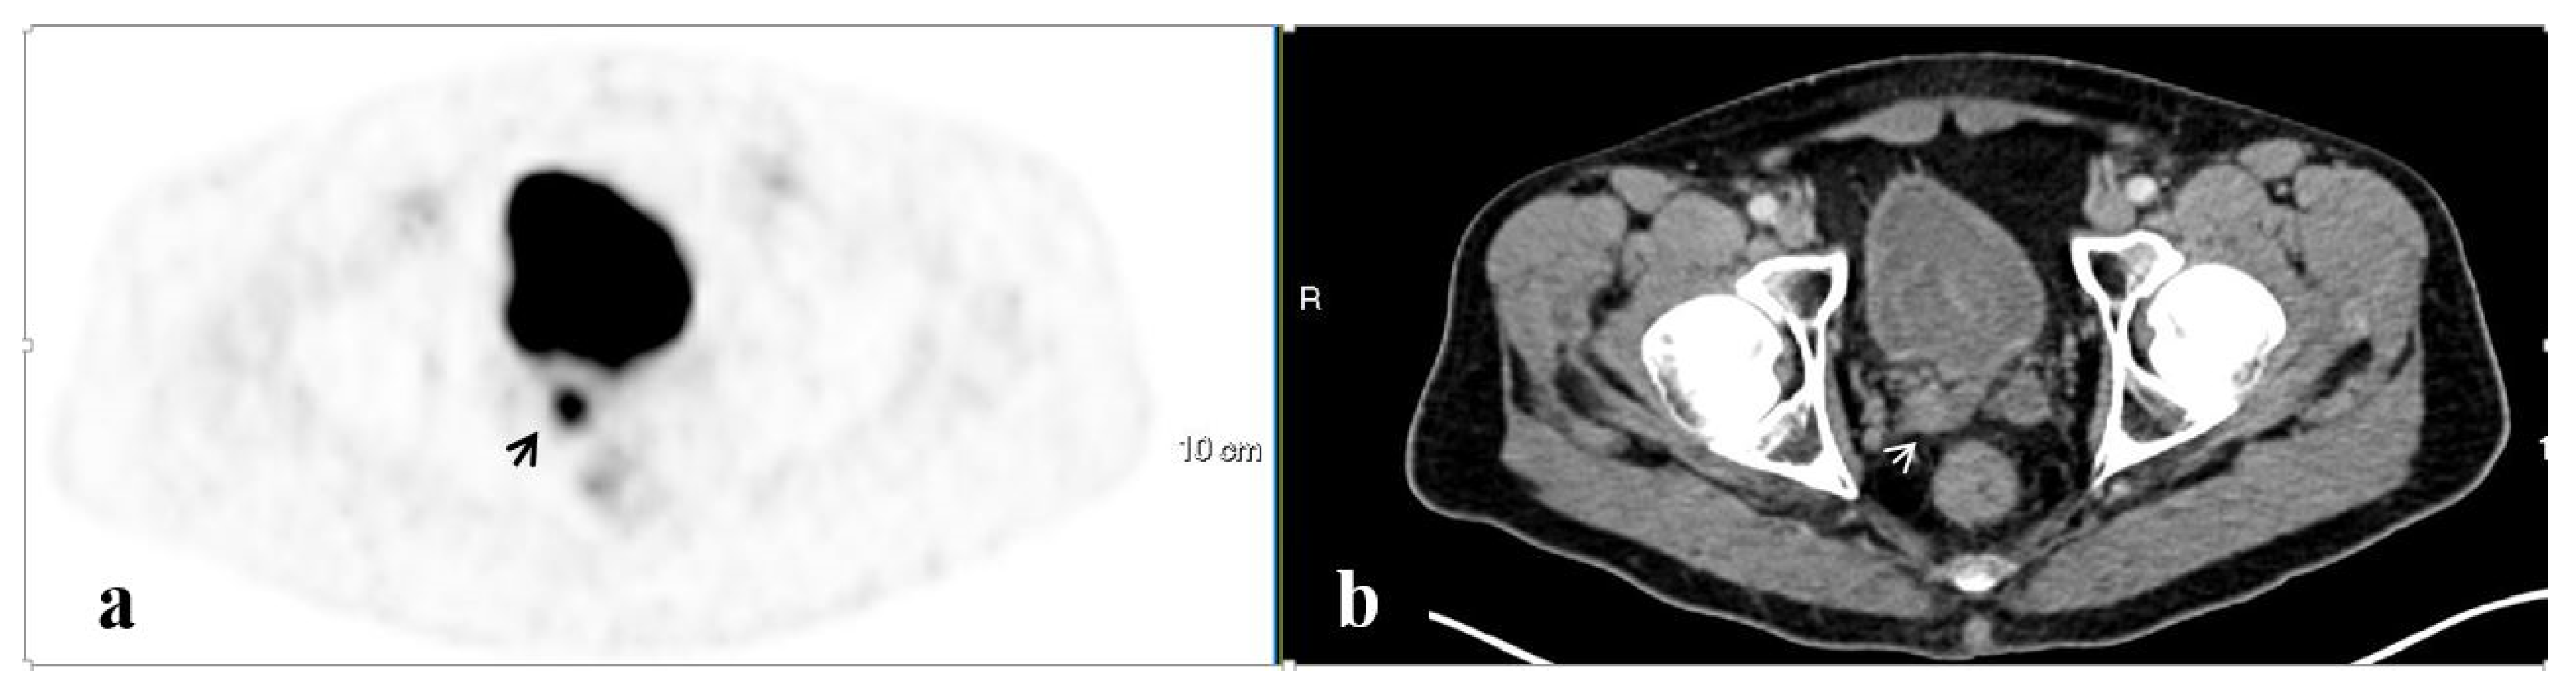

3.4. Salvage Radiation Therapy

3.4.2. The Site of Salvage Radiotherapy

| Isolated pelvic LAD | 43 | 11.0 ± 11.5 | 1.0 ± 0.3 | n/a |